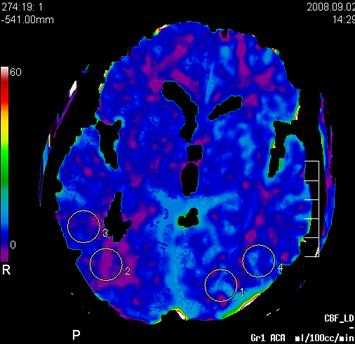

Пример: карта объема мозгового кровотока, с указанием показателей повышения плотности вещества головного мозга во время прохождения быстрого болюса контрастного вещества.

Основными параметрами являются: церебральный кровоток (ЦК), объем церебрального кровотока (ОЦК), среднее время транзита (СВТ) и время до максимума (ВМ).

1. Церебральный кровоток является самым важным параметром. Он показывает количество крови, которое проходит через ткань мозга за определённое время, и измеряется количеством миллилитров крови на 100 г ткани мозга в минуту. Обычно в норме значения для ЦК находятся в пределах 50 - 80 мл крови на 100 г ткани мозга в минуту. Области мозга с большой энергетической потребностью типа кортикальной поверхности или подкорковых узлов имеют иногда значения ЦК в 2 - 3 раза большие значений для белого вещества.

Пример: Пациент С, 52 лет, исследование перфузии мозгового кровотока, немедленное (до 3 часов с момента возникновения очаговой неврологической симптоматики в виде левостороннего гемипареза с элементами моторной афазии).

При проведении стандартного нативного исследования в первые 3 часа истинных признаков развившегося инфаркта (наличия гиподенсивной зоны некроза мозговой ткани, нарушения дифференцировки серого и бело вещества, наличия отека вещества головного мозга, и признаков окклюзии правой СМА) не отмечается.

Однако при проведении немедленной перфузии мозгового кровотока на основании карты объема мозгового кровотока, определяется наличие грубой зоны локальной аперфузии (отсутствия мозгового окруженной зоной гипоперфузии в правом полушарии на уровне базальных ганглиев в проекции височно - теменных отделов правого полушария в территориальном бассейне кровоснабжения правой средней мозговой артерии (правой СМА).